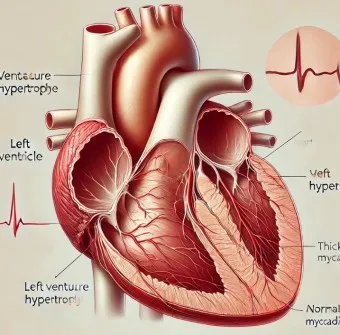

1. 심장 관련 원인

- 부정맥: 정상 심박수 범위 60-100회/분 이탈

- 심장 판막 이상: 증상 발현 시 심박수 변동 20% 이상

- 빈맥증: 휴식 시에도 심박수 100회/분 이상

- 서맥증: 심박수 60회/분 이하로 저하